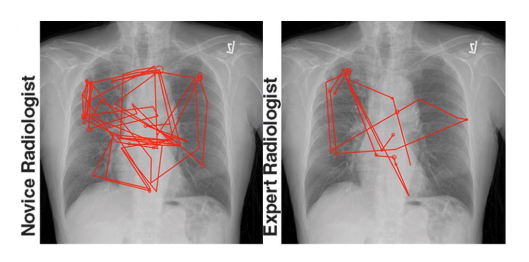

• Expert radiologists use ‘global’ visual processes when viewing scans (study used eye tracking to examine how expert and novice radiologist would view chest X-rays).

• novices used a lot of eye fixation and saccades. Experts had fewer sort of eye fixations so they weren’t sort of stoping and looking at details. Shows that as we become more familiar, we can implement more search strategies.